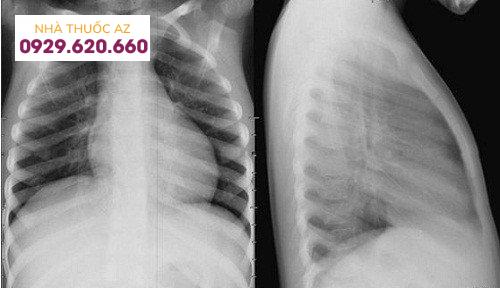

Chụp X-quang

Kỹ thuật này thường được chỉ định khi nghi ngờ tổn thương do ký sinh ở não và phổi (ví dụ: giun lươn não, sán lá phổi…). Chụp X-quang giúp tìm ra dấu hiệu bất thường trên cơ thể, bao gồm giảm độ trong suốt của phổi, các hạch ở kẽ phổi, đốm cản quang nhỏ, mô hình viêm phổi kẽ…

Chụp X-quang là một trong các kỹ thuật chẩn đoán hình ảnh giúp phát hiện ký sinh trùng